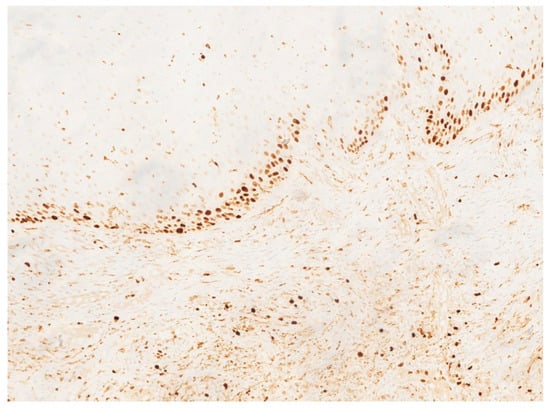

Figure 6.

Immunohistochemical staining for CD34 showing strong and diffuse positivity of the endothelial cells lining the vascular channels, confirming the vascular nature of the lesion.